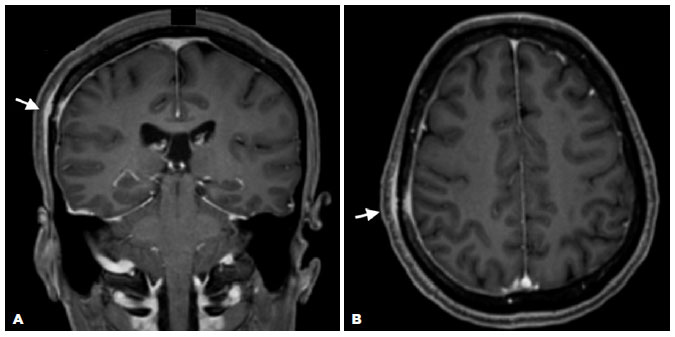

MRI revealed a lesion with impregnation by contrast in the right frontoparietal skullcap and a smooth dural enhancement along the right convexity, suggestive of an inflammatory-infectious process (Figure 2). The cerebral parenchyma and optic nerve-sheath complexes demonstrated no changes. The CSF analysis revealed negative VDRL and FTA-ABS test results, no pleocytosis (5 leukocytes/mm3), and protein levels within the reference values (36,00 mg/dL). The opening pressure was 17 cm H2O.

Admission for intravenous administration of aqueous crystalline penicillin G for 14 days followed, with gradual improvement of signs and symptoms throughout hospitalization (Figure 3A and B). Two months after the treatment, the patient’s VA was 20/20 in OU, resolution of the RPE nodularities was observed on OCT (Figure 3C and D), and complete resolution of the dural enhancement and skull lesion were visualized on MRI (Figure 4). Follow-up in the ophthalmology and infectology departments were maintained.